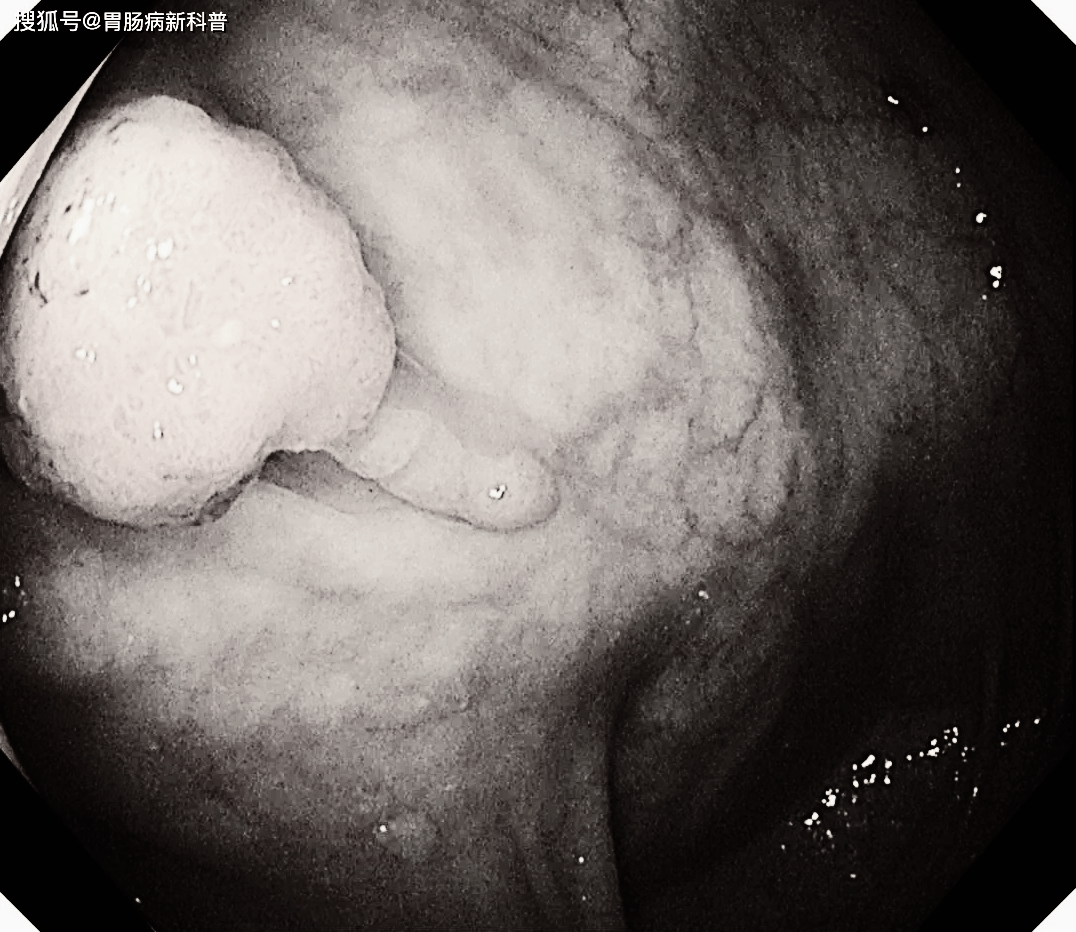

12月31日,还有一例51岁男性,无明显症状,仅仅是长期大便不成形来做检查。

发现距肛门10cm处一凹陷性息肉,当即予以内镜下EMR切除,昨天,病理证实为中分化腺癌。

直肠息肉样隆起

病理报告为腺癌